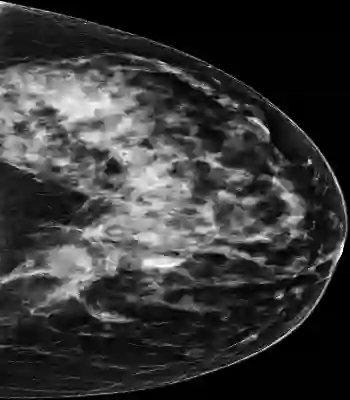

Mammography is used as a standard screening procedure for the potential patients of breast cancer. Over the past decade, it has been shown that deep learning techniques have succeeded in reaching near-human performance in a number of tasks, and its application in mammography is one of the topics that medical researchers most concentrate on. In this work, we propose an end-to-end Curriculum Learning (CL) strategy in task space for classifying the three categories of Full-Field Digital Mammography (FFDM), namely Malignant, Negative, and False recall. Specifically, our method treats this three-class classification as a "harder" task in terms of CL, and create an "easier" sub-task of classifying False recall against the combined group of Negative and Malignant. We introduce a loss scheduler to dynamically weight the contribution of the losses from the two tasks throughout the entire training process. We conduct experiments on an FFDM datasets of 1,709 images using 5-fold cross validation. The results show that our curriculum learning strategy can boost the performance for classifying the three categories of FFDM compared to the baseline strategies for model training.